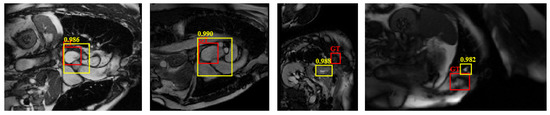

4.4.1. Detection Performance